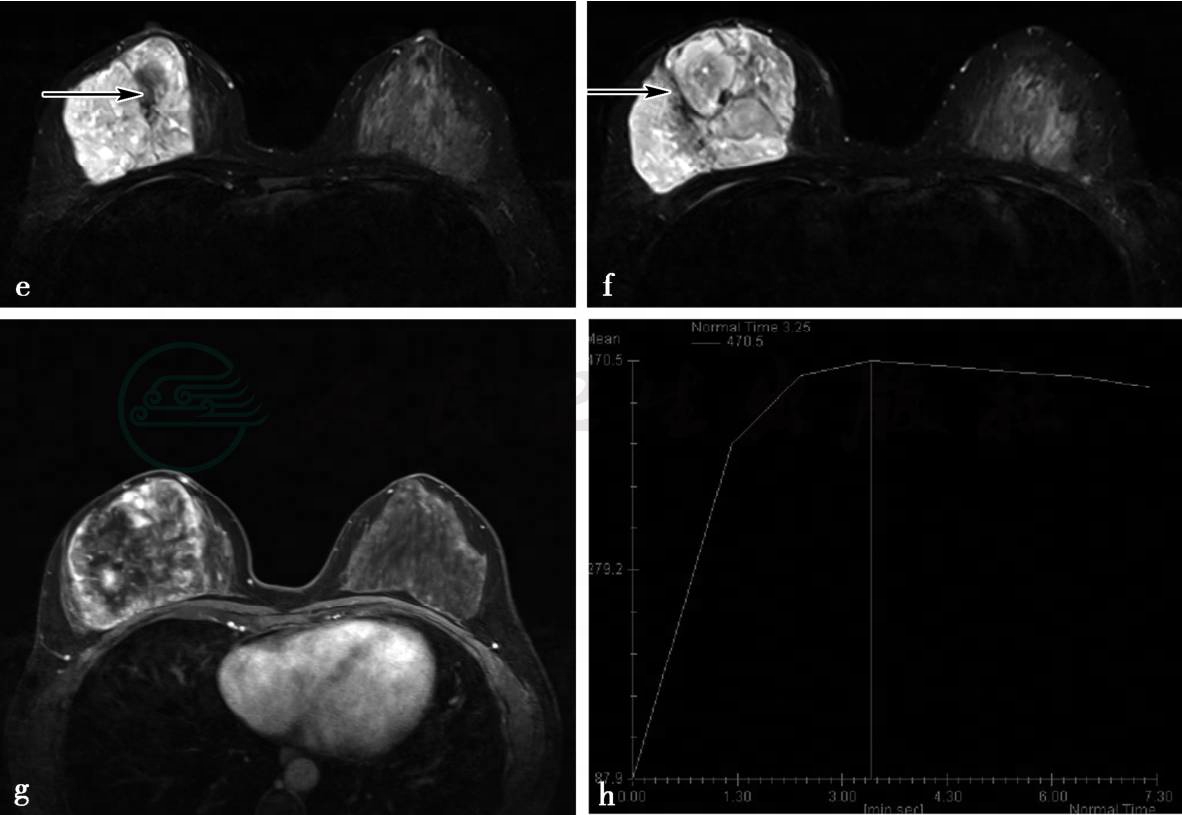

MRI平扫及增强扫描

图2 图2e、f,MRI横断面T2加权成像不同层面,图2g,横断面增强压脂T1加权成像,图2h,TIC曲线。MRI示右乳内巨大分叶状肿块,界清,有完整包膜,信号不均匀,内见囊状间隙(图e箭头所示)及低信号分隔(图f箭头所示),动态增强后呈明显不均匀强化,囊状间隙及分隔无强化,时间—信号强度曲线呈流出型